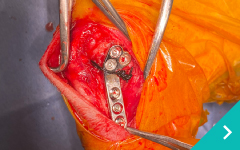

関節鏡を用いた関節内精査と低侵襲手術、関節外法やTPLO法による膝関節再建、MPLG4に対する矯正骨切りを用いた整復、LCPを用いた骨折整復など難易度の高い手術にも対応しております。

関節鏡検査

関節鏡

検査